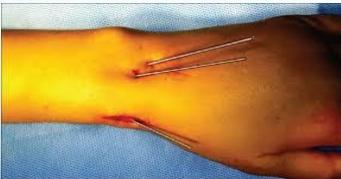

![]() |